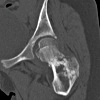

КТ тазобедренного сустава

Сканирование назначается пациентам с подозрением на развитие злокачественных или доброкачественных опухолей проксимального отдела бедренной кости, вертлужной впадины и окружающих мягких тканей. КТ тазобедренного сустава может обнаружить даже небольшие новообразования на доклинической стадии. Также метод эффективен при выявлении метастазов. Томографические исследования широко используются в травматологии, поскольку позволяют диагностировать переломы вертлужной впадины, головы и шеи бедра, в том числе - плохо просматриваемые на обычных рентгенограммах. С помощью КТ можно оценить степень повреждения кости, определить количество отломков, степень тяжести и направление смещения отломков и определить тактику лечения. Кроме того, компьютерная томография назначается пациентам до операции и после хирургического лечения перелома бедра, чтобы оценить эффективность вмешательства.

Дополнительные факты

С помощью КТ можно выявить инфекционные процессы - артрит, остеомиелит. Этот метод диагностики очень информативен и при подозрении на дегенеративно-дистрофические изменения в суставах. Сканирование назначено пациентам с остеопорозом, остеопорозом. Слоистые изображения патологического очага позволяют оценить степень поражения и, основываясь на этих данных, определить последующую схему лечения. Это один из наиболее информативных методов диагностики врожденных аномалий строения этого сустава. КТ показана при подозрении на врожденный вывих бедра и дисплазию бедра. Техника также используется при болезни Пертеса, патологии, которая развивается в контексте нарушения в кровотоке и приводит к асептическому некрозу головки бедренной кости. Чтобы оценить функционирование кровеносных сосудов и состояние сустава в целом, удобнее выполнять сканирование с введением контрастного вещества.